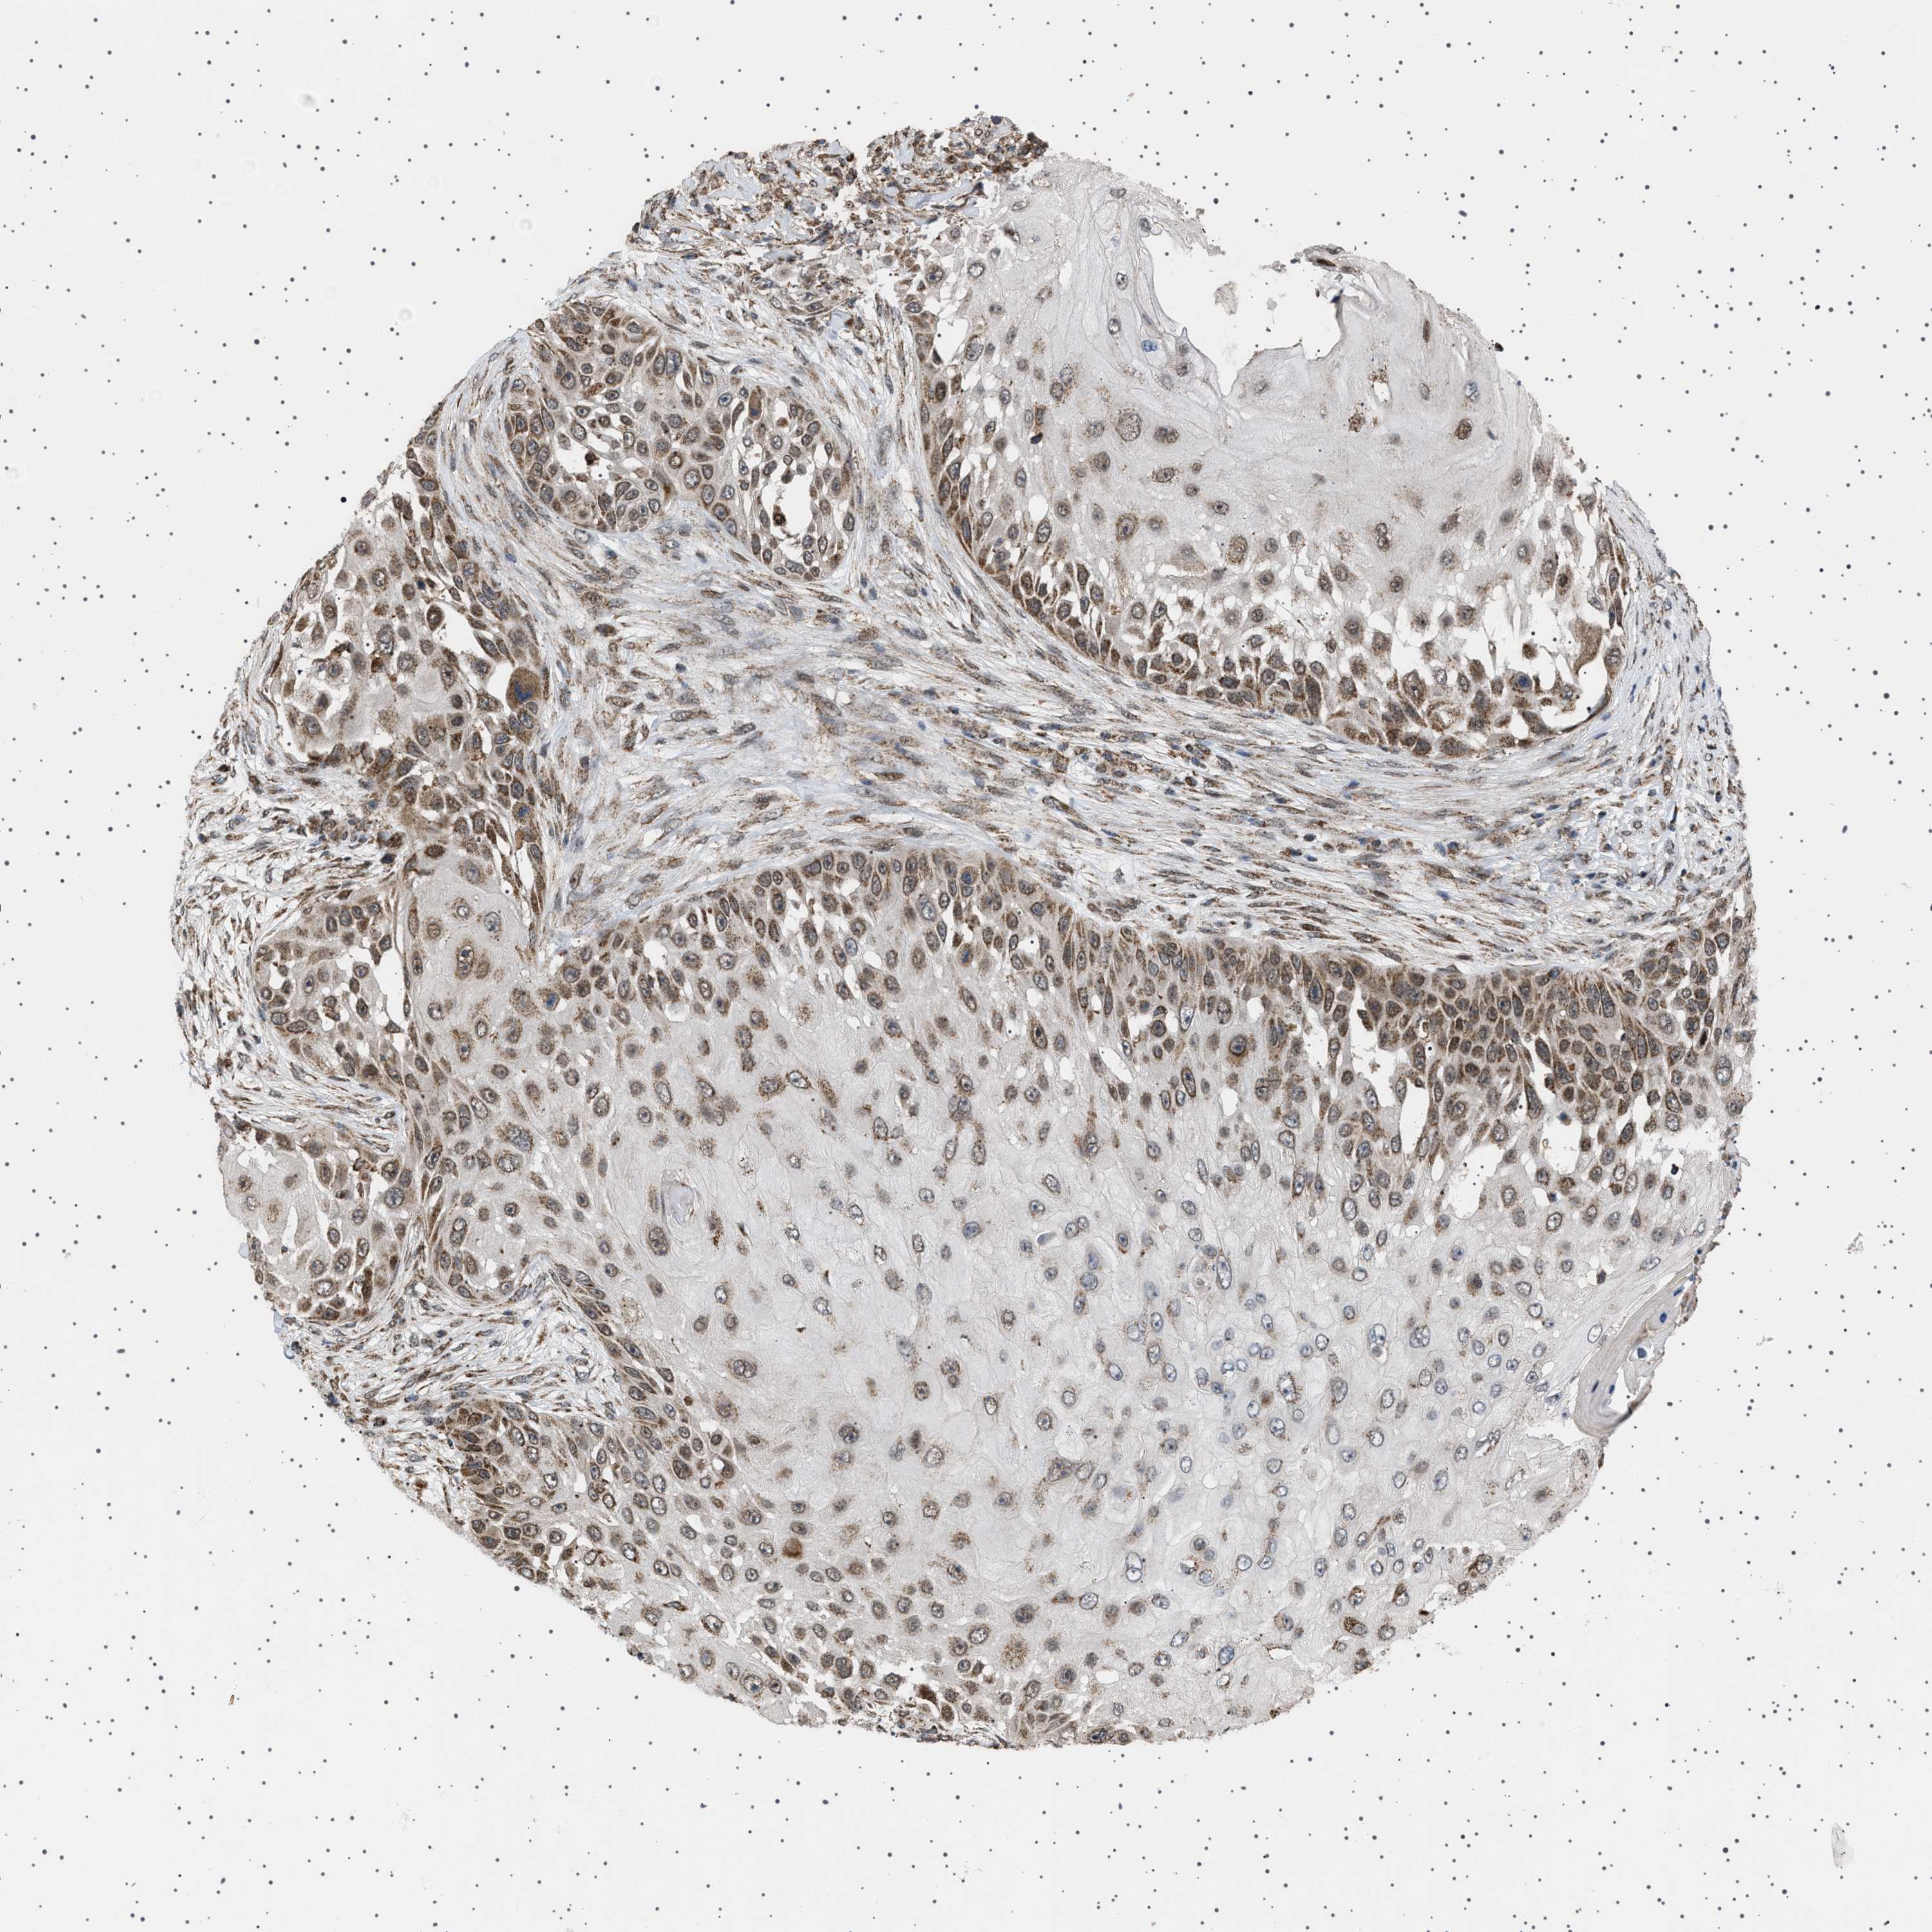

SKIN CANCER - Protein expressioni

A mouse-over function shows sample information and annotation data. Click on an image to view it in a full screen mode. Samples can be filtered based on level of antibody staining by selecting one or several of the following categories: high, medium, low and not detected. The assay and annotation is described here.

Each image is clickable and will lead to virtual microscopy that enables deeper exploration of all samples and also displays staining intensity scores, fraction scores and subcellular localization as well as patient and tissue information for each sample.

Antibody HPA017214

Staining

Medium

Intensity

Moderate

Quantity

75%-25%

Location

Cytoplasmic/membranous

Squamous cell carcinoma, NOS